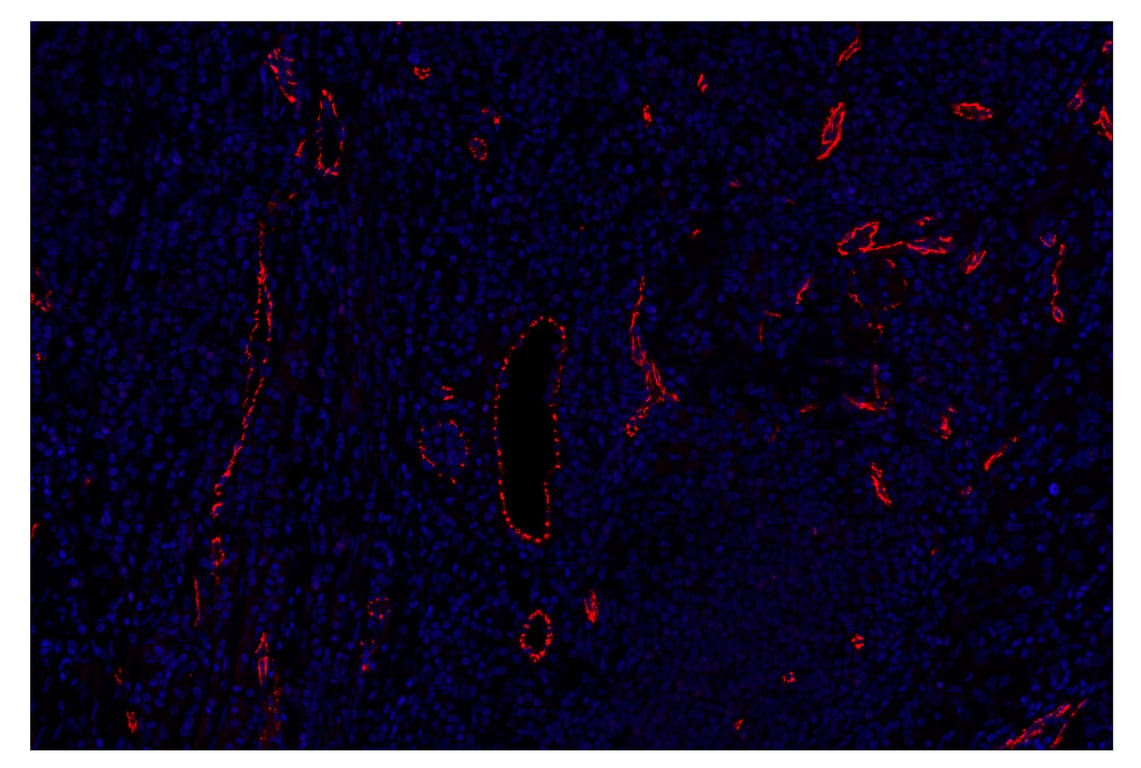

SignalStar™ multiplex immunohistochemical analysis of paraffin-embedded human squamous cell carcinoma of the cervix using VE-Cadherin (E6N7A) & CO-0149-647 SignalStar™ Oligo-Antibody Pair #95571 (red) and DAPI #4083 (blue). All fluorophores have been assigned a pseudocolor, as indicated. Staining was performed on the BOND RX autostainer by Leica Biosystems.

Immunohistochemistry Image 3: VE-Cadherin (E6N7A) & CO-0149-647 SignalStar<sup>™</sup> Oligo-Antibody Pair